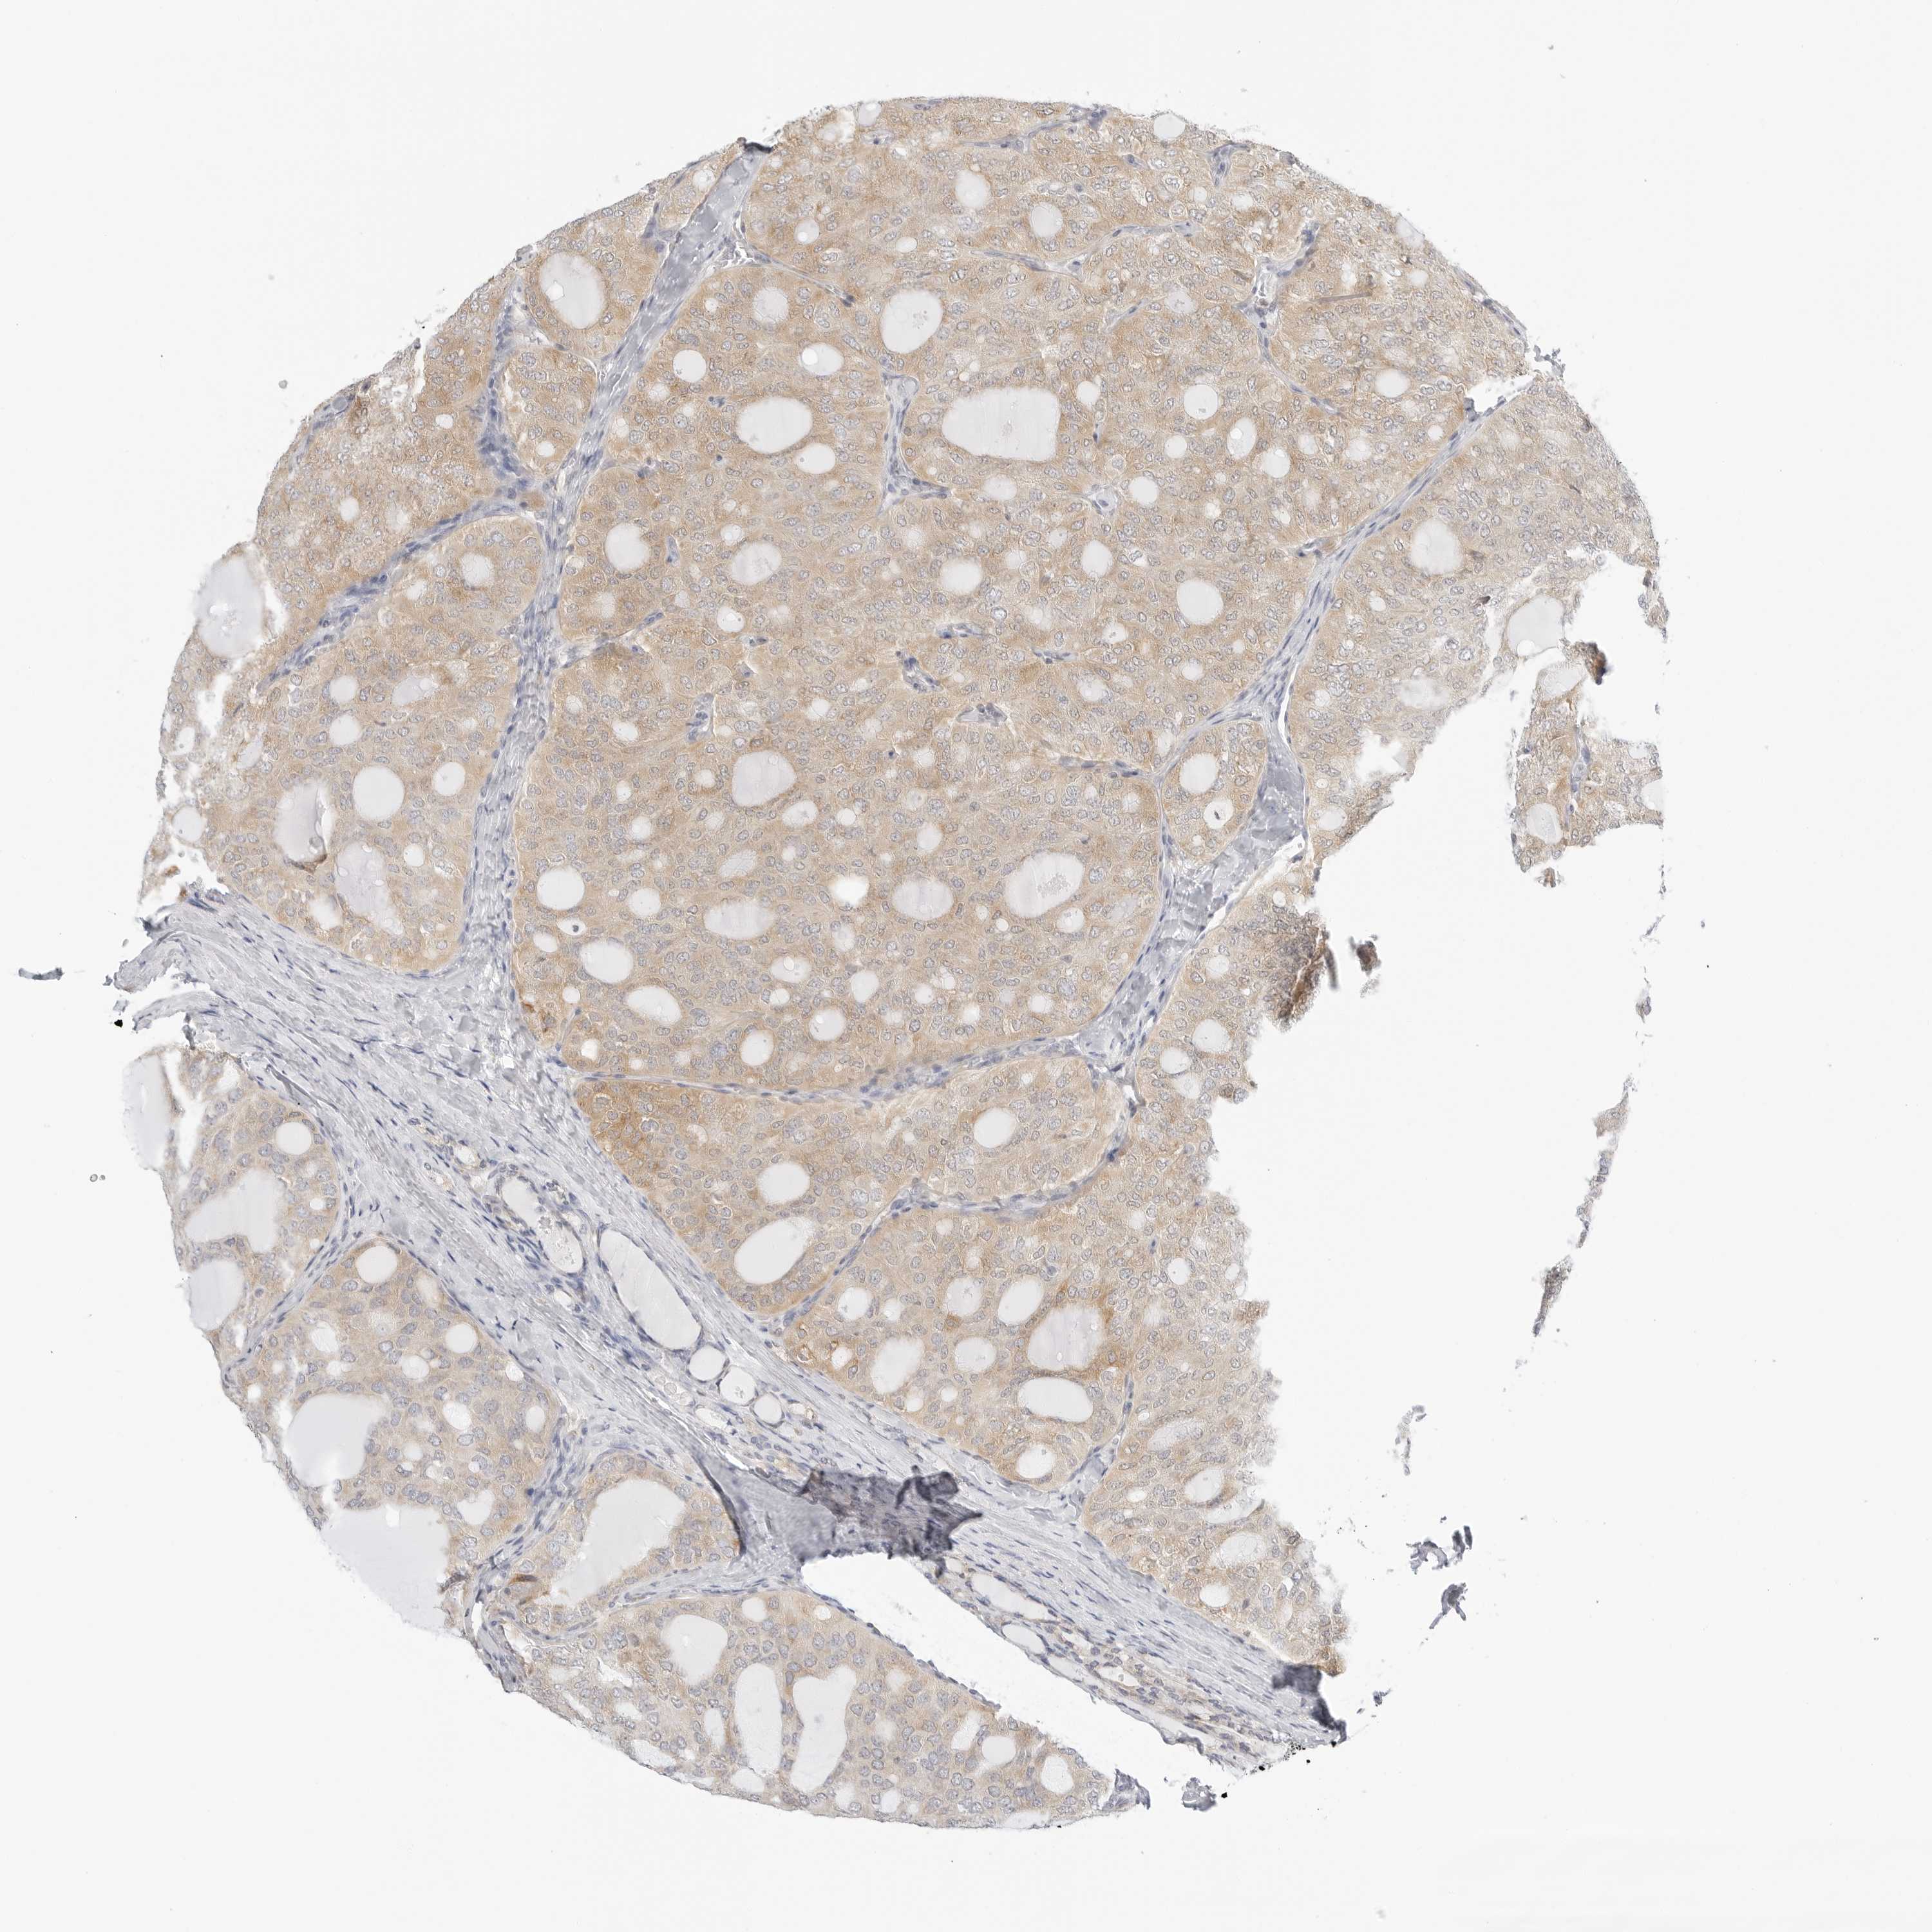

THYROID CANCER - Protein expressioni

A mouse-over function shows sample information and annotation data. Click on an image to view it in a full screen mode. Samples can be filtered based on level of antibody staining by selecting one or several of the following categories: high, medium, low and not detected. The assay and annotation is described here.

Note that samples used for immunohistochemistry by the Human Protein Atlas do not correspond to samples in the TCGA dataset.

Antibody stainingi

Antibody staining in the annotated cell types in the current human tissue is reported as not detected, low, medium, or high, based on conventional immunohistochemistry profiling in selected tissues. This score is based on the combination of the staining intensity and fraction of stained cells.

Each image is clickable and will lead to virtual microscopy that enables deeper exploration of all samples and also displays staining intensity scores, fraction scores and subcellular localization as well as patient and tissue information for each sample.

Antibody HPA028161

Staining

High

Medium

Low

Not detected

Intensity

Strong

Moderate

Weak

Negative

Quantity

>75%

75%-25%

<25%

None

Location

Nuclear

Cytoplasmic/membranous

Cytoplasmic/membranous,nuclear

Papillary adenocarcinoma, NOS

Follicular adenoma carcinoma, NOS